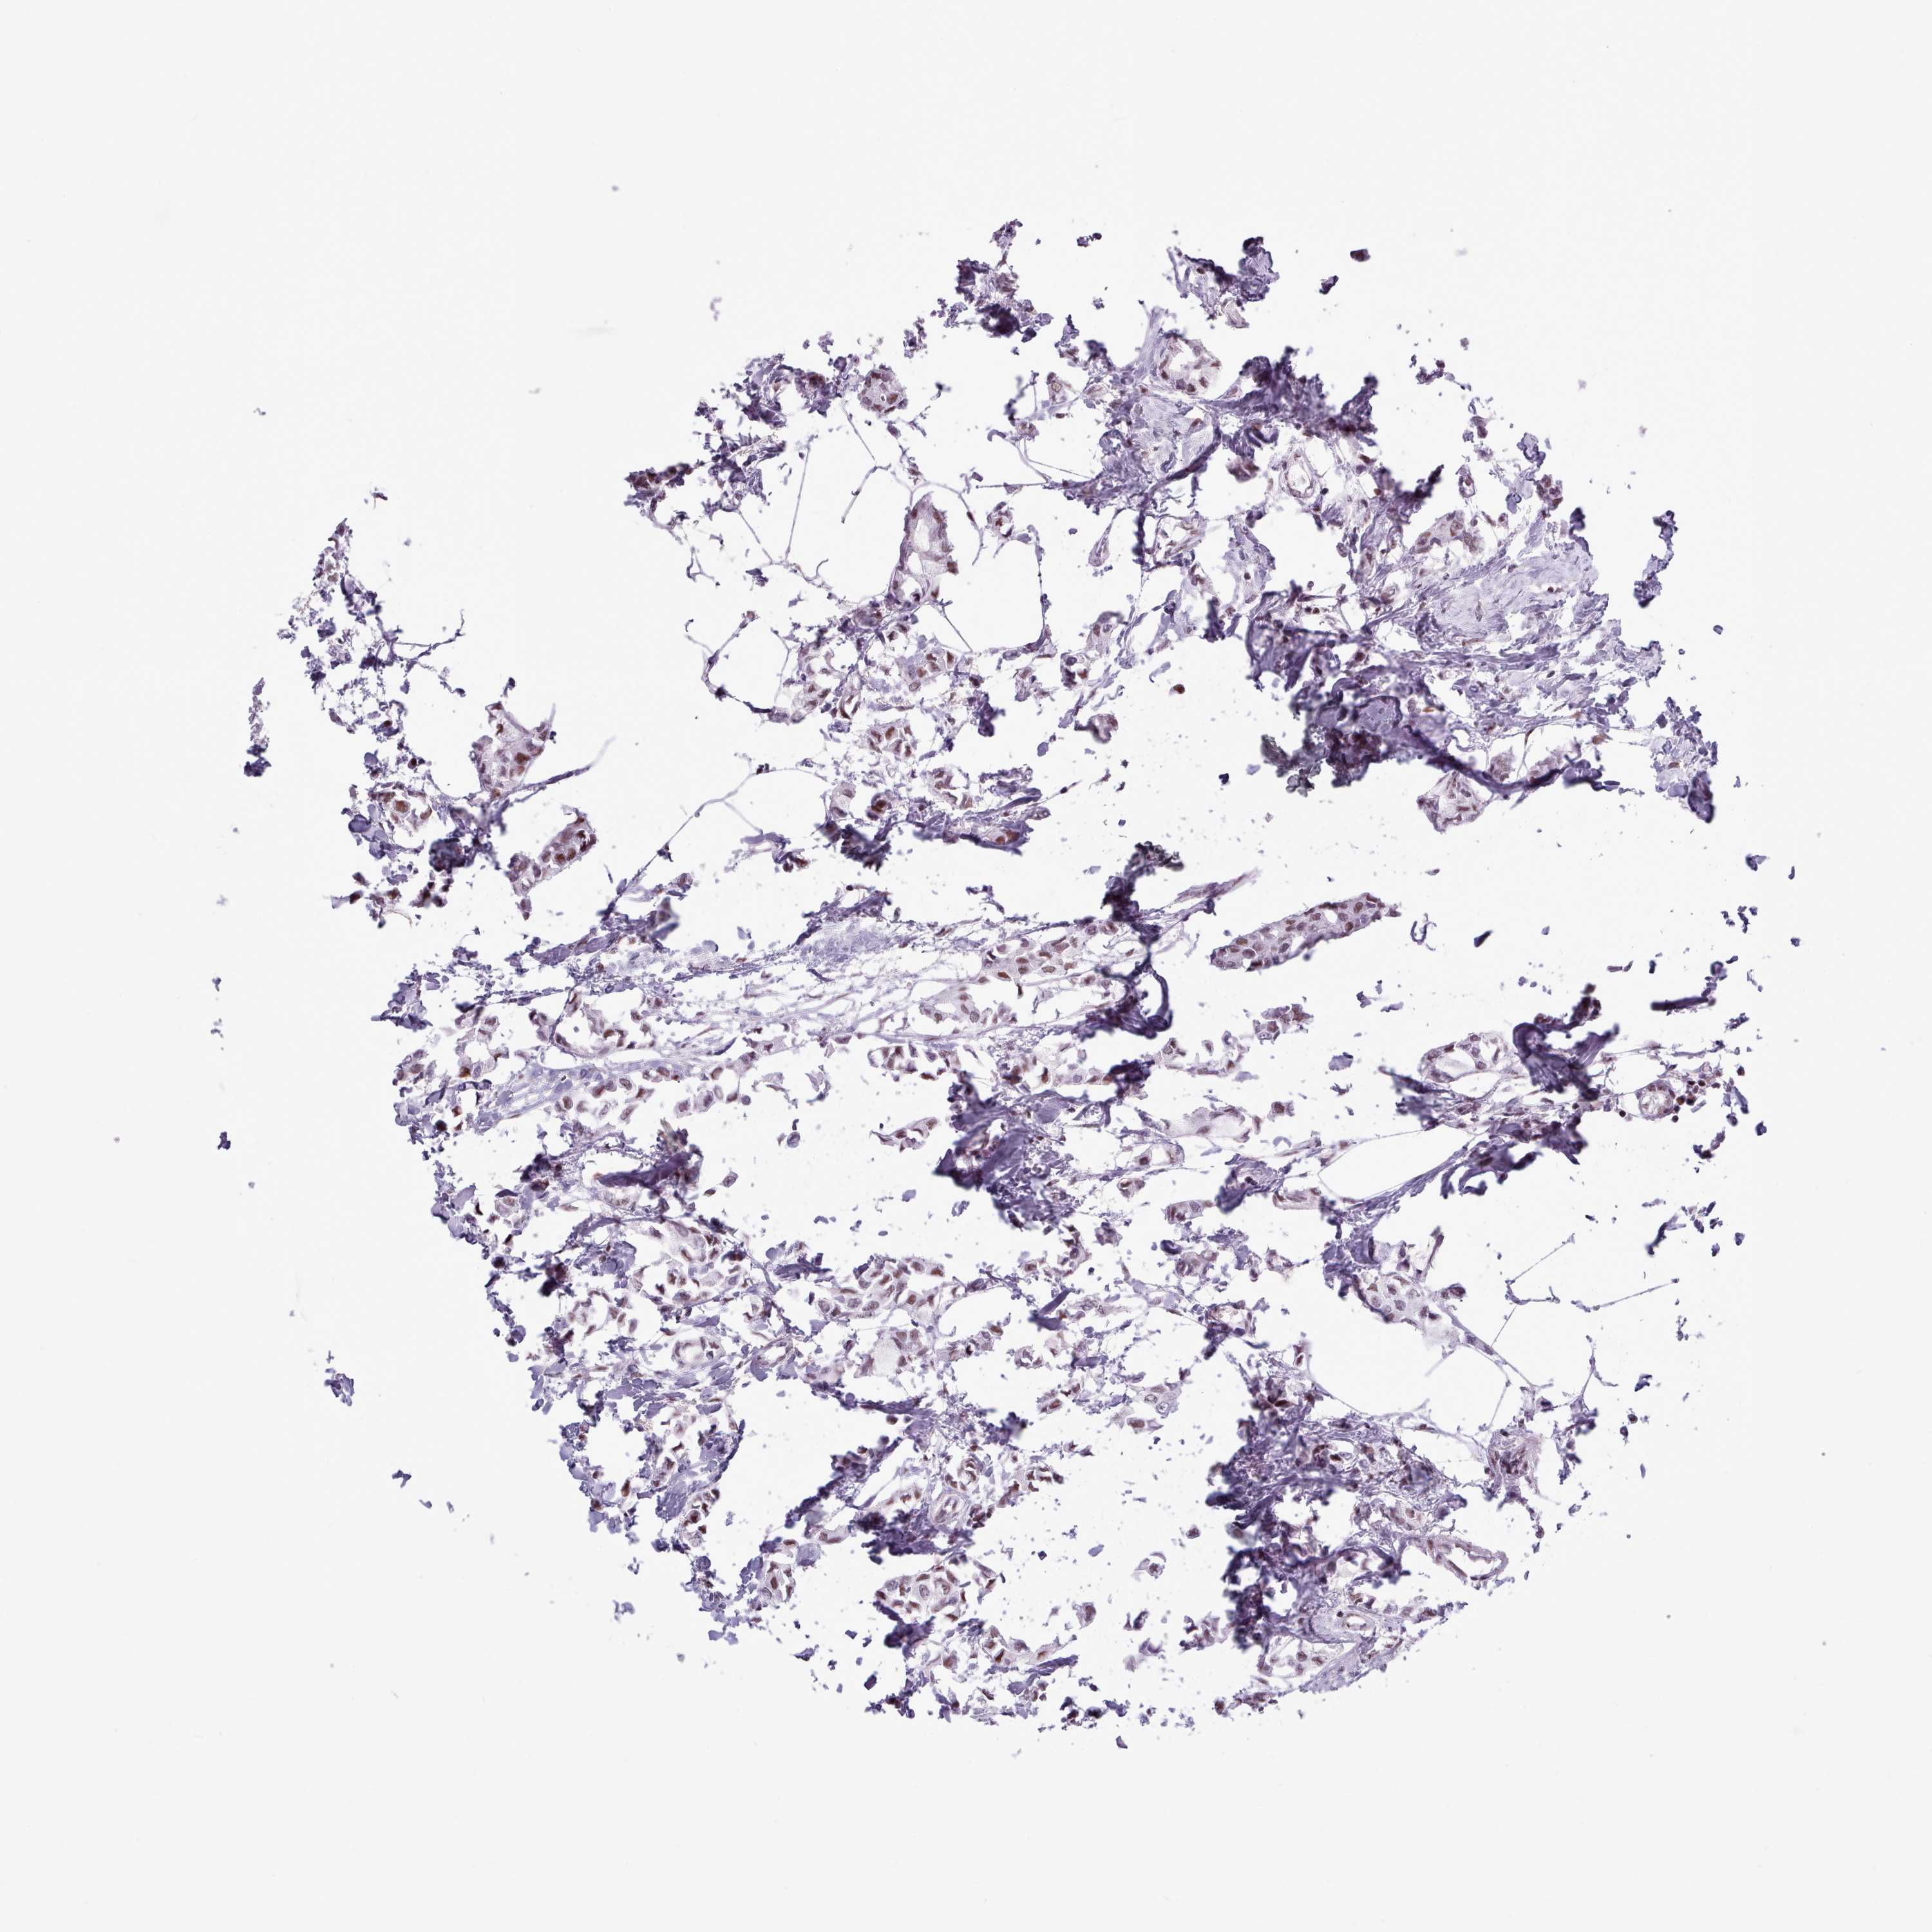

BRCA TCGA BRCA VALIDATION PROTEIN EXPRESSION

ANTIBODIES

AND

VALIDATION